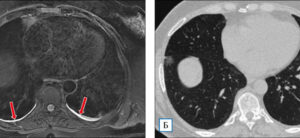

Рассасывающая терапия при пневмонии у взрослых

Физиотерапия при лечении пневмонии — это методика, в которой используются природные и природные факторы окружающей среды. Эффективность этой методики давно доказана на практике. Способствует уменьшению отечности, успокаивает воспалительные процессы, положительно влияет на иммунную систему пациента, восстанавливает дыхательные функции. Приступать к физиотерапевтическим процедурам можно только после стихания острой фазы болезни. Именно в это время этот метод …